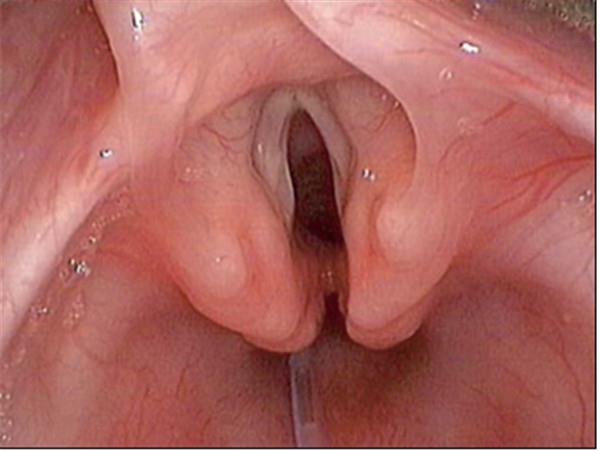

常見(jiàn)的鏡下改變:

喉裂

聲門(mén)下狹窄